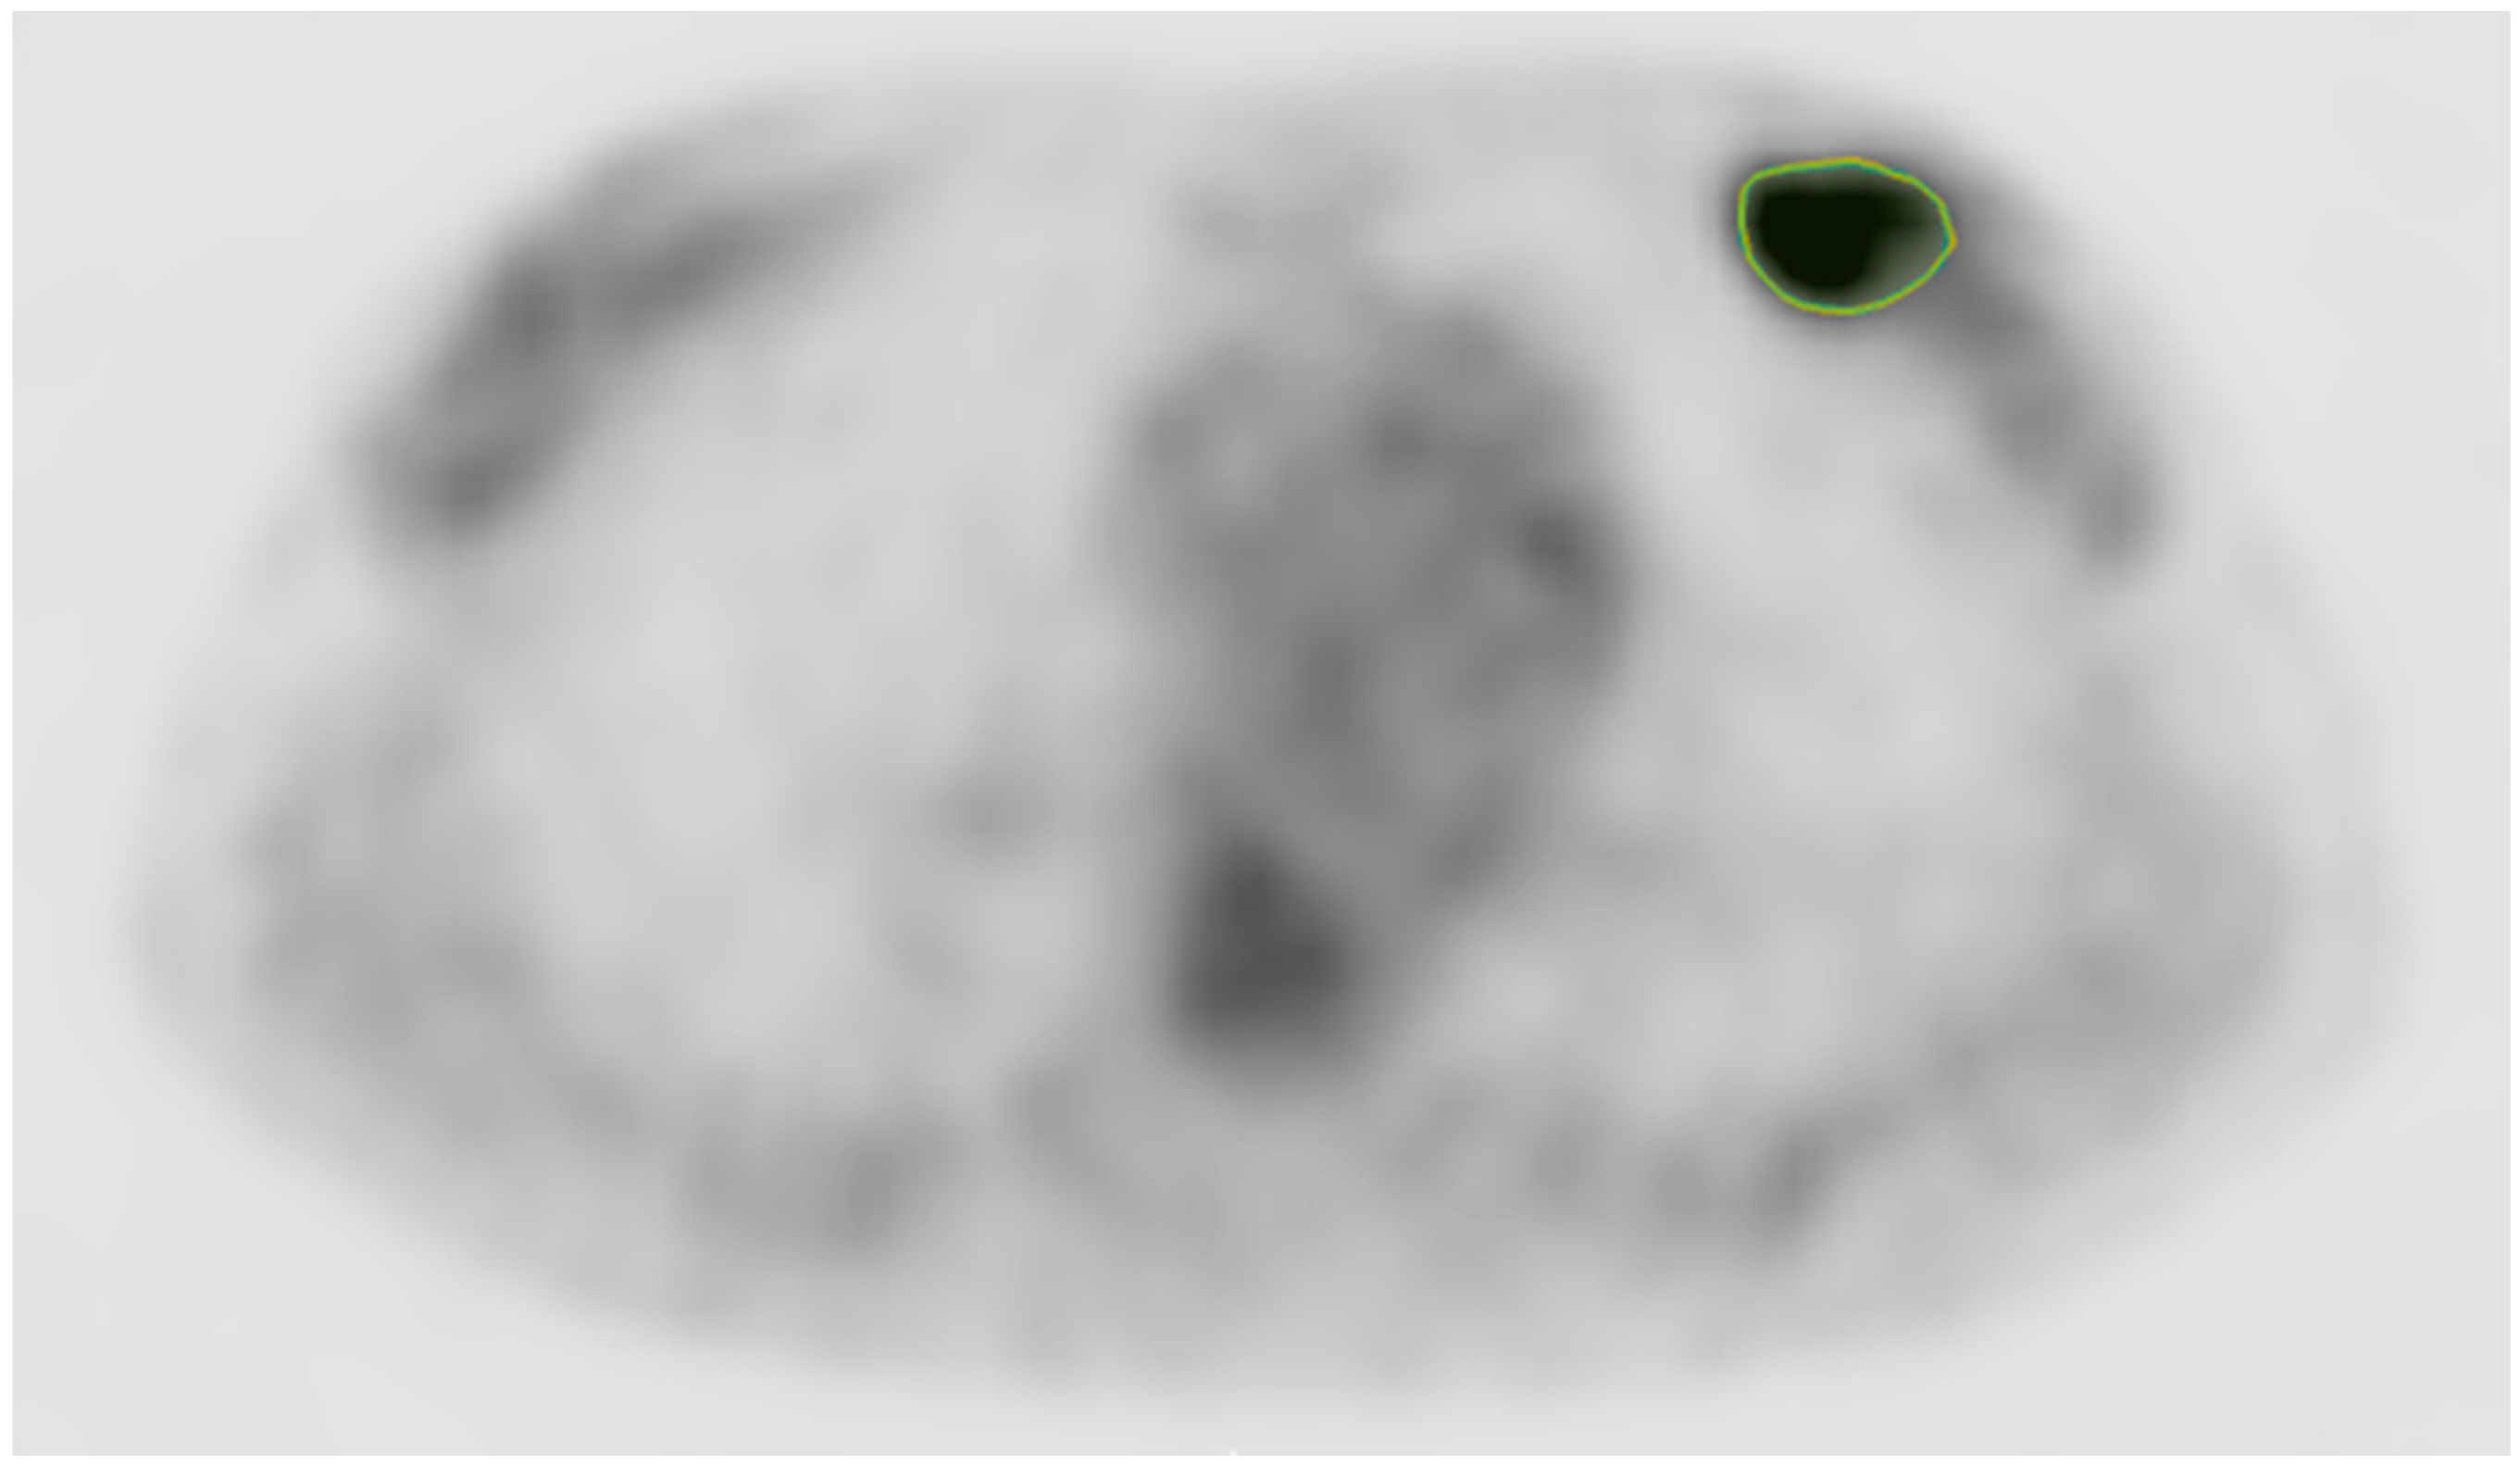

2.4. Imaging Processing and Radiomic Features

| Tumor SUVmax | 10.0 (7.2, 14.8) |

| Metabolic tumor volume (cm3) | 7.9 (3.8, 18.9) |